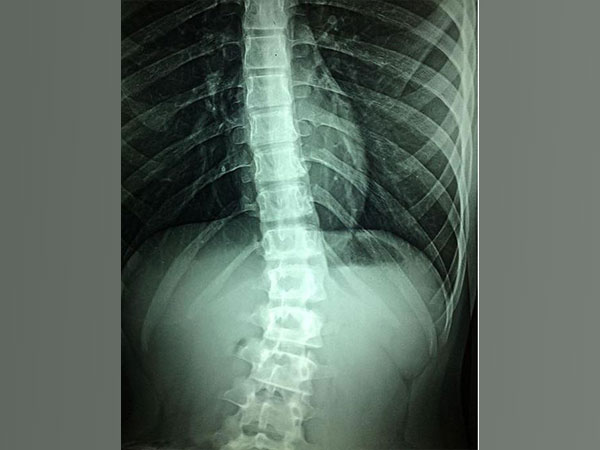

Children, teenagers getting spinal surgery don't need so many opioids: Study